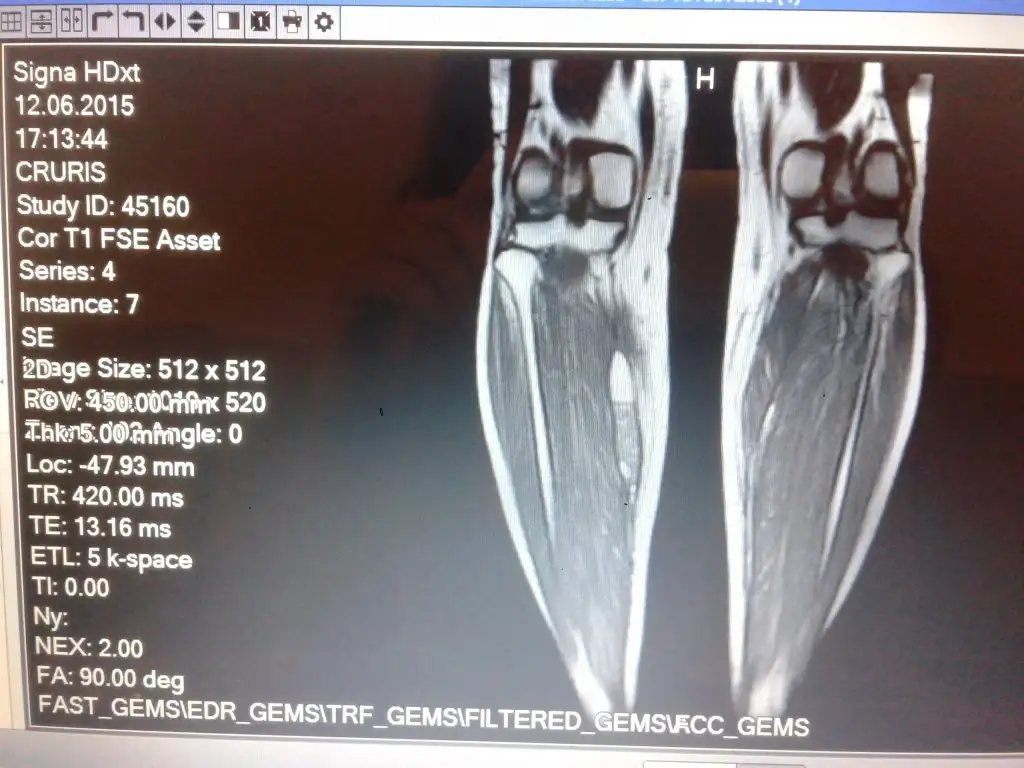

Arkadaşlarım ben 2 kez talihsiz silikon op. geçirdim hatırlarsanız.3. de ise çıkarttırdım. şimdi sağ bacağımda bir sertlik vardı ki bu başından beri vardı. sol bacağımda yoktu. fakat bu sertlik 2 ay önce daha büyük , ağrılı ve kalın hale geldiler. mr çektirdim. silikonun konulduğu yerde kas arasında bir kitle görünüyor. kitlenin duvarı mevcut. 9 cm uzunluğunda 2 cm. kalınlığında. gittiğim dr.lar özellikle ortopedistle yorum yapamıyor. bizim alanımız değil diye yapan kişiye gidin diyorlar. . bir estetikçiye gittim o da aynı şeyleri söyledi biz bun müdahele etmeyiz dedi. bunun kapsül kontraktürü olabileceğini ama onun da silikon çıkarma esnasında çizildiğini bu şekilde vücudun yoketmesinin kolaylaştığını söyledi. şuan kadar önlem alınmış olsaydı yokolmuş olması gerektiğini söyledi.benim 9 ay oldu . lokal kortizon olabilirmiş o da sadece ağrıyı kesmesi için. o da zaten benim önerdiğim birşey değil doku harabiyeti yapıyor diye. siz ameliyatınızı yapan dr. a gidin diyorlar. nasıl bir şeyin içindeyiz inanın bilmiyorum. Yaptırıyoruz ama Allah'a emanetiz. yaptırsan bir dert yaptırmasan bir dert. çıkartıp kurtulduğunu sanarsın ama kurtulamazsın.

mr. fotosu koydum. bilen varsa bir baksın lütfen. ekrana göre solda kalıyor. Memede olsa müdahale ediliyormuş bu nasıl çıkıcak oradan? dizarkası kesilse yeniden nasıl alınacak? Bu yeniden bir ameliyat demek benim için. Baldır yarılıp mı alınacak ordan, nasıl? mr 1.webp

mr. fotosu koydum. bilen varsa bir baksın lütfen. ekrana göre solda kalıyor. Memede olsa müdahale ediliyormuş bu nasıl çıkıcak oradan? dizarkası kesilse yeniden nasıl alınacak? Bu yeniden bir ameliyat demek benim için. Baldır yarılıp mı alınacak ordan, nasıl? Eki Görüntüle 1572303